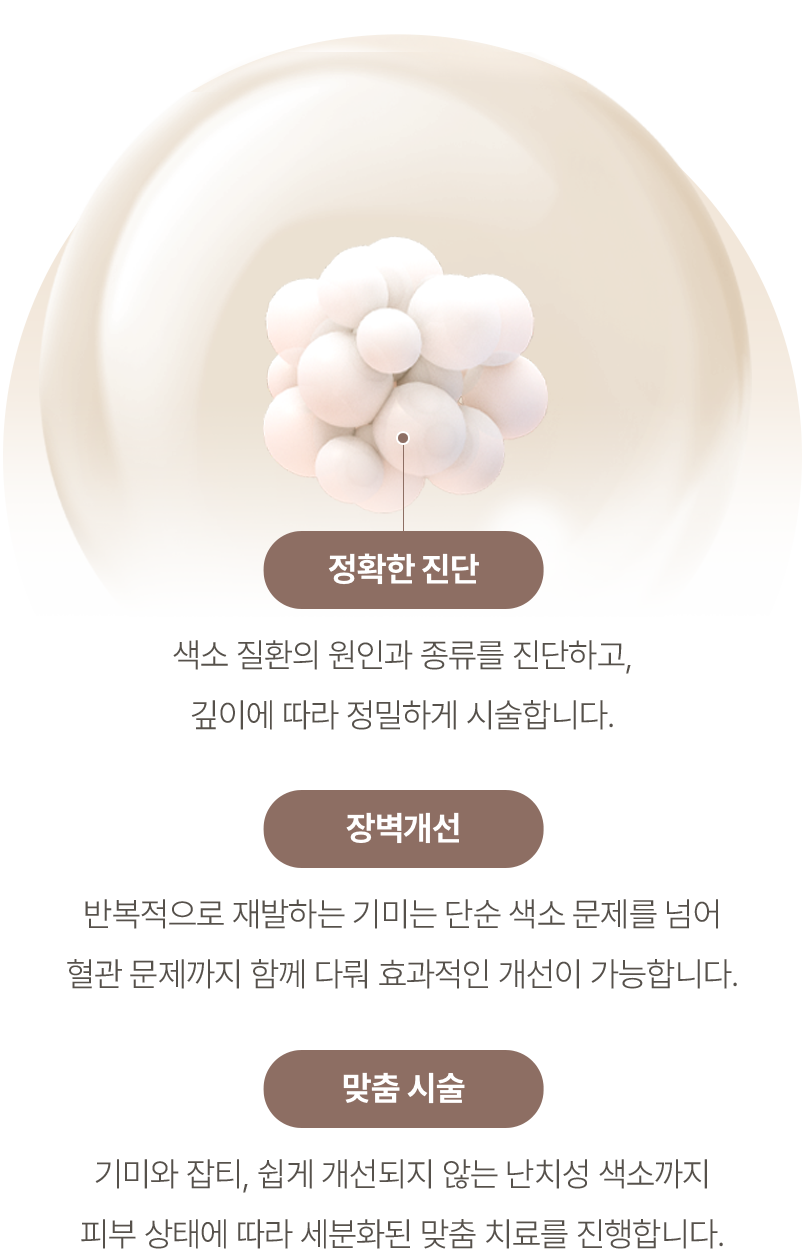

정밀 피부 진단 장비와 분석을 통해 피부 상태

(수분, 유분, 모공, 색소 등)를 정밀하게 분석합니다.

피부분석 데이터를 기반으로 개인의 피부 타입을

고려한 맞춤형 복합 레이저 치료 플랜을 설계합니다.

설계된 치료 계획에 따라 조합한 맞춤 시술을 시행하여

최적의 치료 효과를 유도합니다.

마크뷰는 고해상도 촬영과 분석 기술을 통해

모공, 색소, 탄력, 유수분 밸런스 등 피부 상태를 객관적으로 진단합니다.

보이지 않는 피부 속 문제까지 정밀하게 확인해, 치료 전후 변화도 정확히 비교할 수 있습니다.

민앤정의원은 이 데이터를 기반으로 1:1 맞춤 커스터마이징 플랜을 설계해

더 효과적인 결과를 이끌어냅니다.

마크뷰 진단기는 전 광원 LED를 채용해 기존 플래시 방식보다 촬영 전후의 비교가 훨씬 정밀합니다.

또한, 미세 밝기 조절이 가능한 일반광 LED를 사용해 피부 밝기 측정의 정확도가 높아지고, 섬세한 피부 톤 분석이 가능합니다.

특히 자외선 광(365nm)을 통해 여드름균이 배출하는 포피린 형광 파장을 감지함으로써, 눈에 보이지 않는 여드름 유발 요인까지 정확히 진단할 수 있습니다.